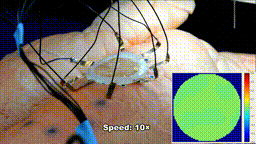

EIT柔性传感器

费了这么大一番力气打印在器官表面上的电子传感器当然不一般。如下图所示,这种电子柔性传感器由离子水凝胶与EIT技术结合制成的,能够检测并监视器官的健康状况。